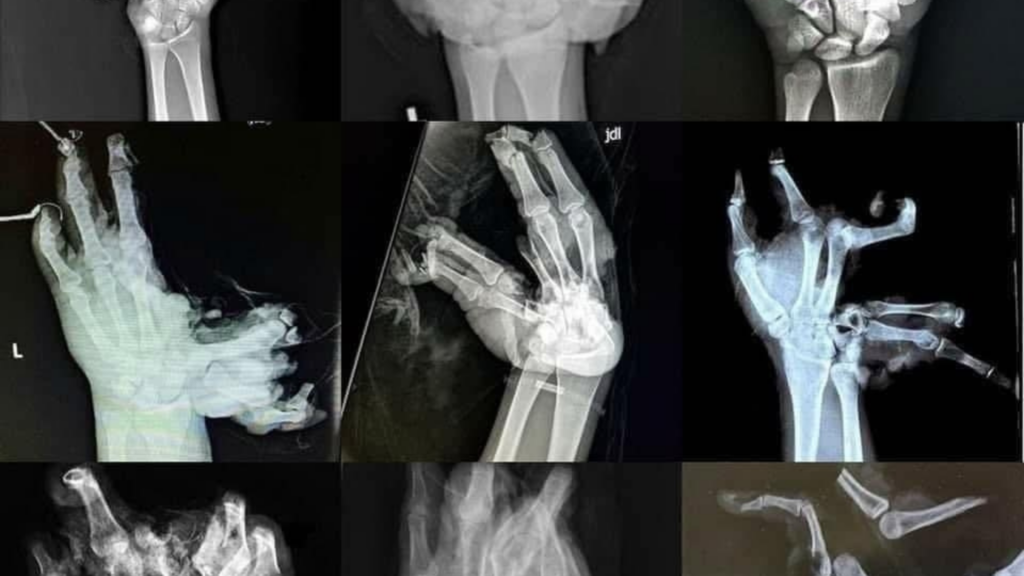

Along with the statement, Derieuw shared an image of X-rays of the hands of victims of firework accidents to illustrate the physical consequences of the misuse of the explosives.

"Every year, the emergency services treat serious injuries caused by the unsafe use of fireworks," he said. "A moment of carelessness can lead to permanent, irreversible injuries."

Image of x-rays of hands after a firework accident. Credit: Brussels Fire Brigade